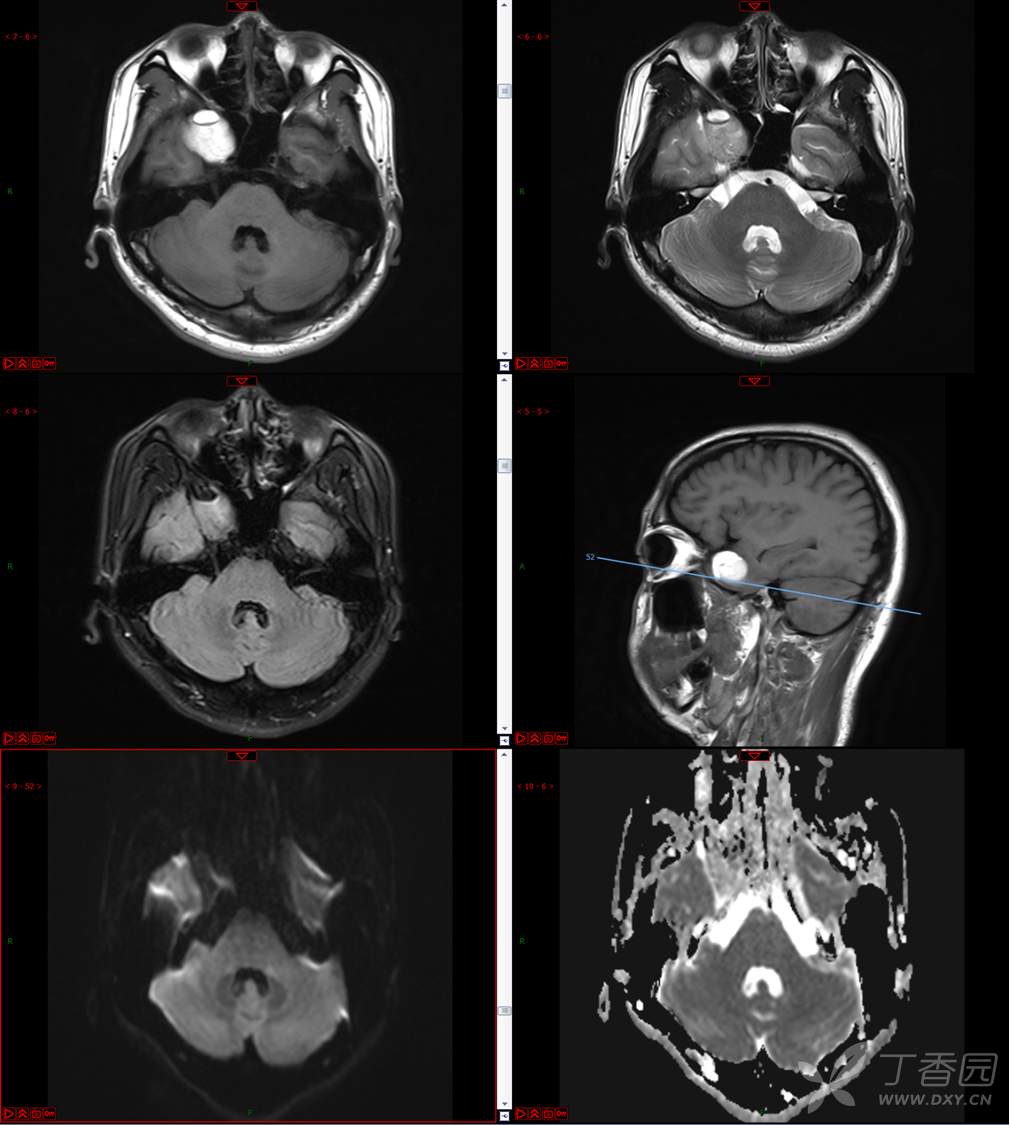

【影诊笔记534】青年男性,视物模糊就诊,CT、MRI、MRS齐全,请分析~~~

主 诉:视物重影5天。

现病史:患者5天前无明显诱因出现视物重影,表现为右视时视物成双,无头痛、头晕,无恶心、呕吐,无面部麻木、饮水呛咳等,于当地医院就诊,行颅脑MR示“颅内占位性病变”,现为求进一步治疗来诊。患者病来精神可,饮食、睡眠正常,体重无明显变化。